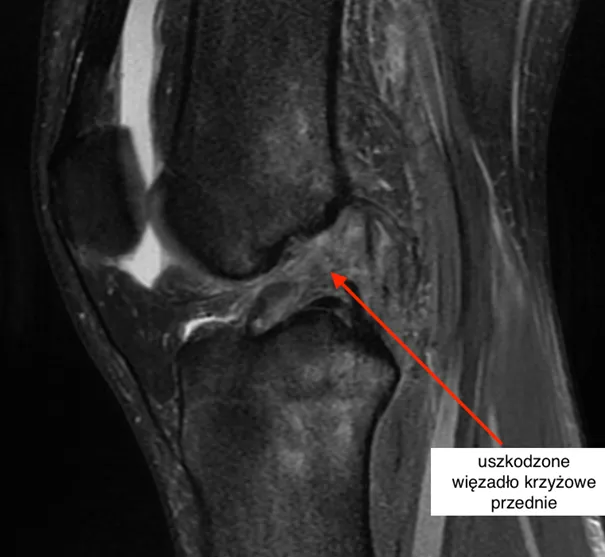

| Stopień III (ciężkie skręcenie) | Całkowite zerwanie więzadła (np. więzadła krzyżowego przedniego - ACL, więzadła pobocznego przyśrodkowego - MCL). Objawy to silny ból (czasem paradoksalnie ustępujący tuż po zerwaniu więzadła), duży obrzęk, znacząca niestabilność stawu, uczucie "uciekania" kolana. Często wymaga leczenia operacyjnego. | 6-12 miesięcy. Pełny powrót do sprawności po leczeniu zachowawczym lub operacyjnym jest długotrwały. Ból może być przewlekły, jeśli rehabilitacja jest niewystarczająca. |

Skręcenie stopnia III to najpoważniejszy uraz, charakteryzujący się całkowitym zerwaniem jednego lub więcej więzadeł. Ból jest zazwyczaj bardzo silny, choć paradoksalnie, tuż po zerwaniu więzadła, może on chwilowo ustąpić z powodu uszkodzenia zakończeń nerwowych. Towarzyszy mu duży obrzęk, znaczna niestabilność stawu i uczucie "uciekania" kolana. Leczenie często wymaga interwencji chirurgicznej, po której następuje długotrwała rehabilitacja. Pełny powrót do sprawności, zwłaszcza do aktywności sportowych, może trwać od 6 do 12 miesięcy. Ból może stać się przewlekły, jeśli rehabilitacja jest niewystarczająca, nieprawidłowo prowadzona, lub jeśli doszło do powikłań. W takich przypadkach konieczna jest ponowna konsultacja z lekarzem i specjalistą od rehabilitacji.Nie tylko ból: inne objawy skręcenia kolana

Uczucie "uciekania", "chwiejności" lub niestabilności kolana jest bardzo niepokojącym objawem, który najczęściej sygnalizuje poważniejsze uszkodzenie więzadeł, zwłaszcza więzadła krzyżowego przedniego (ACL) lub więzadła pobocznego (MCL), typowe dla skręceń stopnia II i III. Oznacza ono, że struktury odpowiedzialne za stabilizację stawu nie są w stanie utrzymać go w prawidłowej pozycji podczas obciążenia lub ruchu. To uczucie powinno stopniowo ustępować w miarę postępów w leczeniu i rehabilitacji, gdy uszkodzone więzadła się goją, a mięśnie stabilizujące staw są wzmacniane. Jeśli uczucie niestabilności utrzymuje się pomimo rehabilitacji, jest to silny sygnał, że konieczna jest dalsza diagnostyka i ewentualna interwencja chirurgiczna.